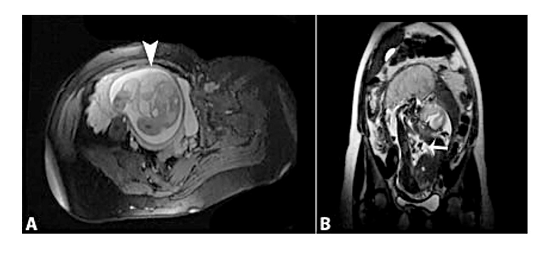

There was no evidence of any other fetal anomalies. The fetal thorax and intra-abdominal organs were normal in the magnetic resonance imaging (MRI) examination (Figure 2).

The distinctive imaging feature of the lymphatic malformation is the absence of blood flow, which is observed with the use of color Doppler ultrasonography to distinguish it from hemangioma.5 In this case, the fetal MRI also provided more information about the infiltration of the lesion to the fetal thoracal structures, and complemented the role of sonography. Traditionally, ultrasonography has been used as the primary screening method for prenatal diagnosis. MRI may provide information about both the anatomy and the extension of the lesion, thus providing the information essential for parental counselling.3 Also, 3D ultrasound helped to identify the lesion clearly and completely, and make the consultation with pediatric surgeons and parents more comprehensive.2